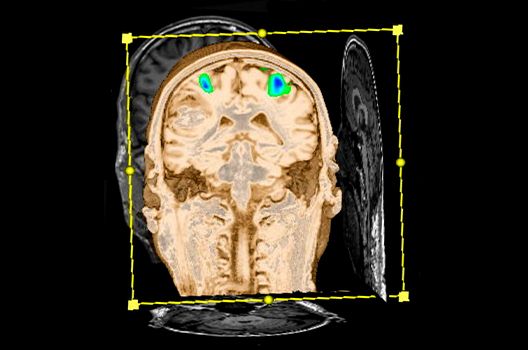

- Intraoperative Magnetresonanztomographie

Zudem ist das Universitätsklinikum Tübingen das erste Zentrum Europas mit einem deckenmontierten intraoperativen Hochfeld-Magnetresonanztomographen, mit dem bereits während einer Hirnoperation MRT-Bilder angefertigt und ausgewertet werden können. In enger Kooperation mit der hiesigen Neurochirurgie können wir somit zu nahezu jedem Zeitpunkt der OP die genaue Lagebeziehung zu wichtigen anatomischen Strukturen darstellen und das Resektionsausmaß überprüfen.